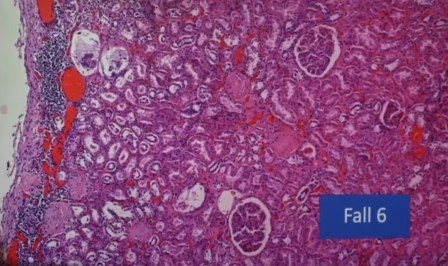

Infiltración e inflamación renal, no en los glomérulos, sino nefritis intersticial

Los linfocitos están alrededor del glomérulo pero no lo afectan directamente